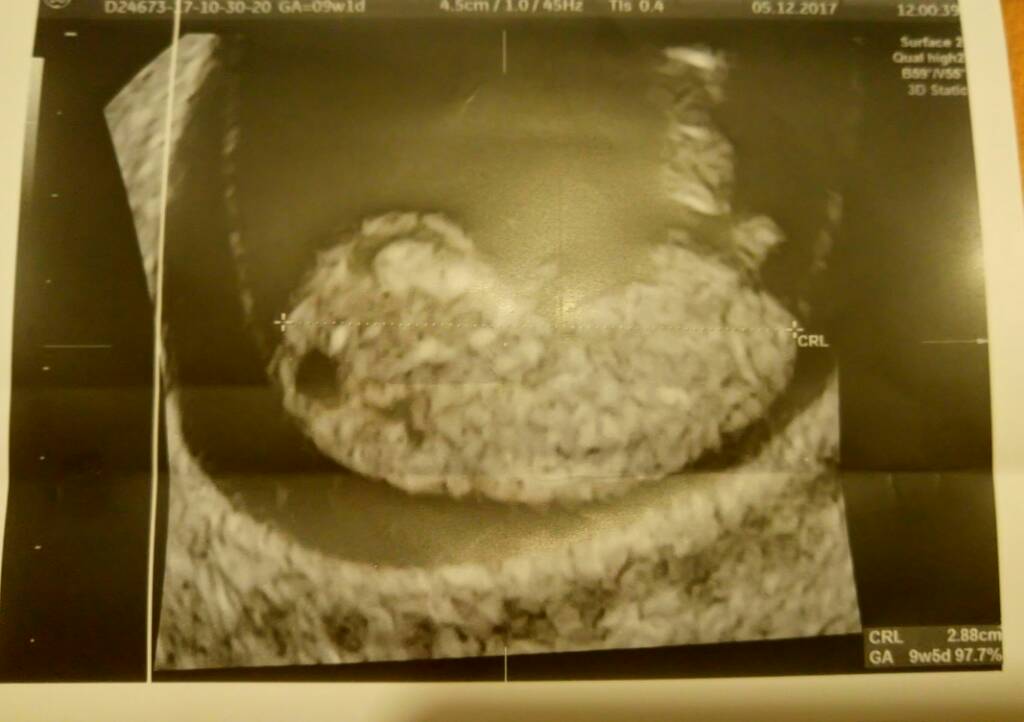

Hej dziewczyny ;) przedstawiam wam moją już nie fasolkę :) z OM 9+1 z USG 9+5 :) i póki co wszystko dobrze :)

1512481211-9cfebf34e1fa7925-aaaaaa.jpeg